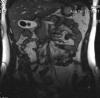

мистерсвин Опубликовано 6 июня, 2009 Жалоба Share Опубликовано 6 июня, 2009 Лучшие свиные нарезки !!!!! сейчас уже нет ни пузыря, ни камней. SvinInside.rar.zip Ссылка на комментарий Поделиться на другие сайты More sharing options...

Fiend Опубликовано 6 июня, 2009 Жалоба Share Опубликовано 6 июня, 2009 Хоули щет! Черный - это булыжник? Ссылка на комментарий Поделиться на другие сайты More sharing options...

мистерсвин Опубликовано 7 июня, 2009 Жалоба Share Опубликовано 7 июня, 2009 два чёрных. они кстати, прикольные - лёгкие такие (плавали же там), жёлтые с красивыми узорами на поверхности ! сам всю жизнь полировал и растил у меня нет фото с макро, чтобы их близко снять Ссылка на комментарий Поделиться на другие сайты More sharing options...

F.E.A.R Machine Опубликовано 7 июня, 2009 Жалоба Share Опубликовано 7 июня, 2009 нихрена себе! здоровенные какие! А как они проявляли себя? ps: такая неразбериха оказывается внутрях Ссылка на комментарий Поделиться на другие сайты More sharing options...

мистерсвин Опубликовано 7 июня, 2009 Жалоба Share Опубликовано 7 июня, 2009 Большие никак, а маленькие затыкали желчный проток и начиналась желтуха. Плюс еще панкреатические приступы боли, но об этом вспоминать не хочется. Ссылка на комментарий Поделиться на другие сайты More sharing options...